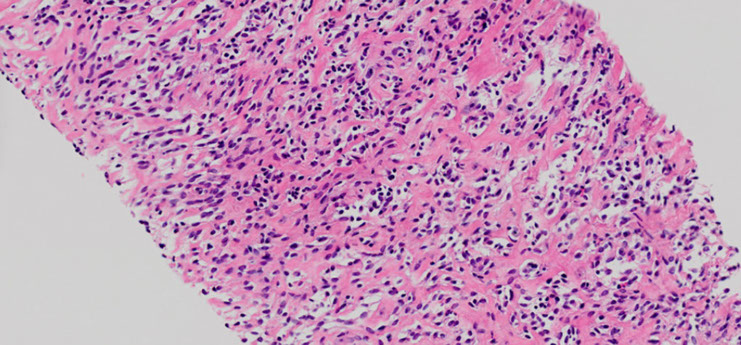

Solitary Fibrous Tumor (SFT)

Sarcomatoid carcinomas

Best to dx specific subtype rather than the general "sarcomatoid ca" to avoid confusion c sarcoma

- sarcomatoid ca's are rare (<1% of all lung ca's)

- can't dx pleomorphic, spindle cell or giant cell ca and is very difficult to dx carcinosarc or pulmonary blastoma on bx or cyto

Px is poor for all these tumors

Pleomorphic Ca

Poorly differentiated NSCC c at least 10% spindle and/or giant cells

Spindle cell Ca

Almost pure population of epithelial spindle cells c no differentiated carcinomatous elements

Giant cell Ca

Almost entirely made of giant cells / MNGCs with no differentiated carcinomatous elements

Carcinosarcoma

Mix of SCC/adenoca and sarcoma (rhabdomyosarcoma, chondrosarcoma, osteosarcoma)

- clonal tumors that develop from sarcomatoid change in a carcinoma

Genes: usually has TP53 mutations

- less common are KRAS and EGFR muations

Pulmonary blastoma

Biphasic tumor c (low grade) fetal adenocarcinoma and primitive mesenchymal stroma

- may have sarcomatous elements, but not necessary to dx

Genes: CTNNB1 exon 3 missense mutation which activates Wnt pathway by B-catenin aberrant nuclear/cytoplasmic localization

- this is also seen in well-differentiated fetal adenoca

- may also see TP53 mutation c p53 and MDM2 protein accumulation